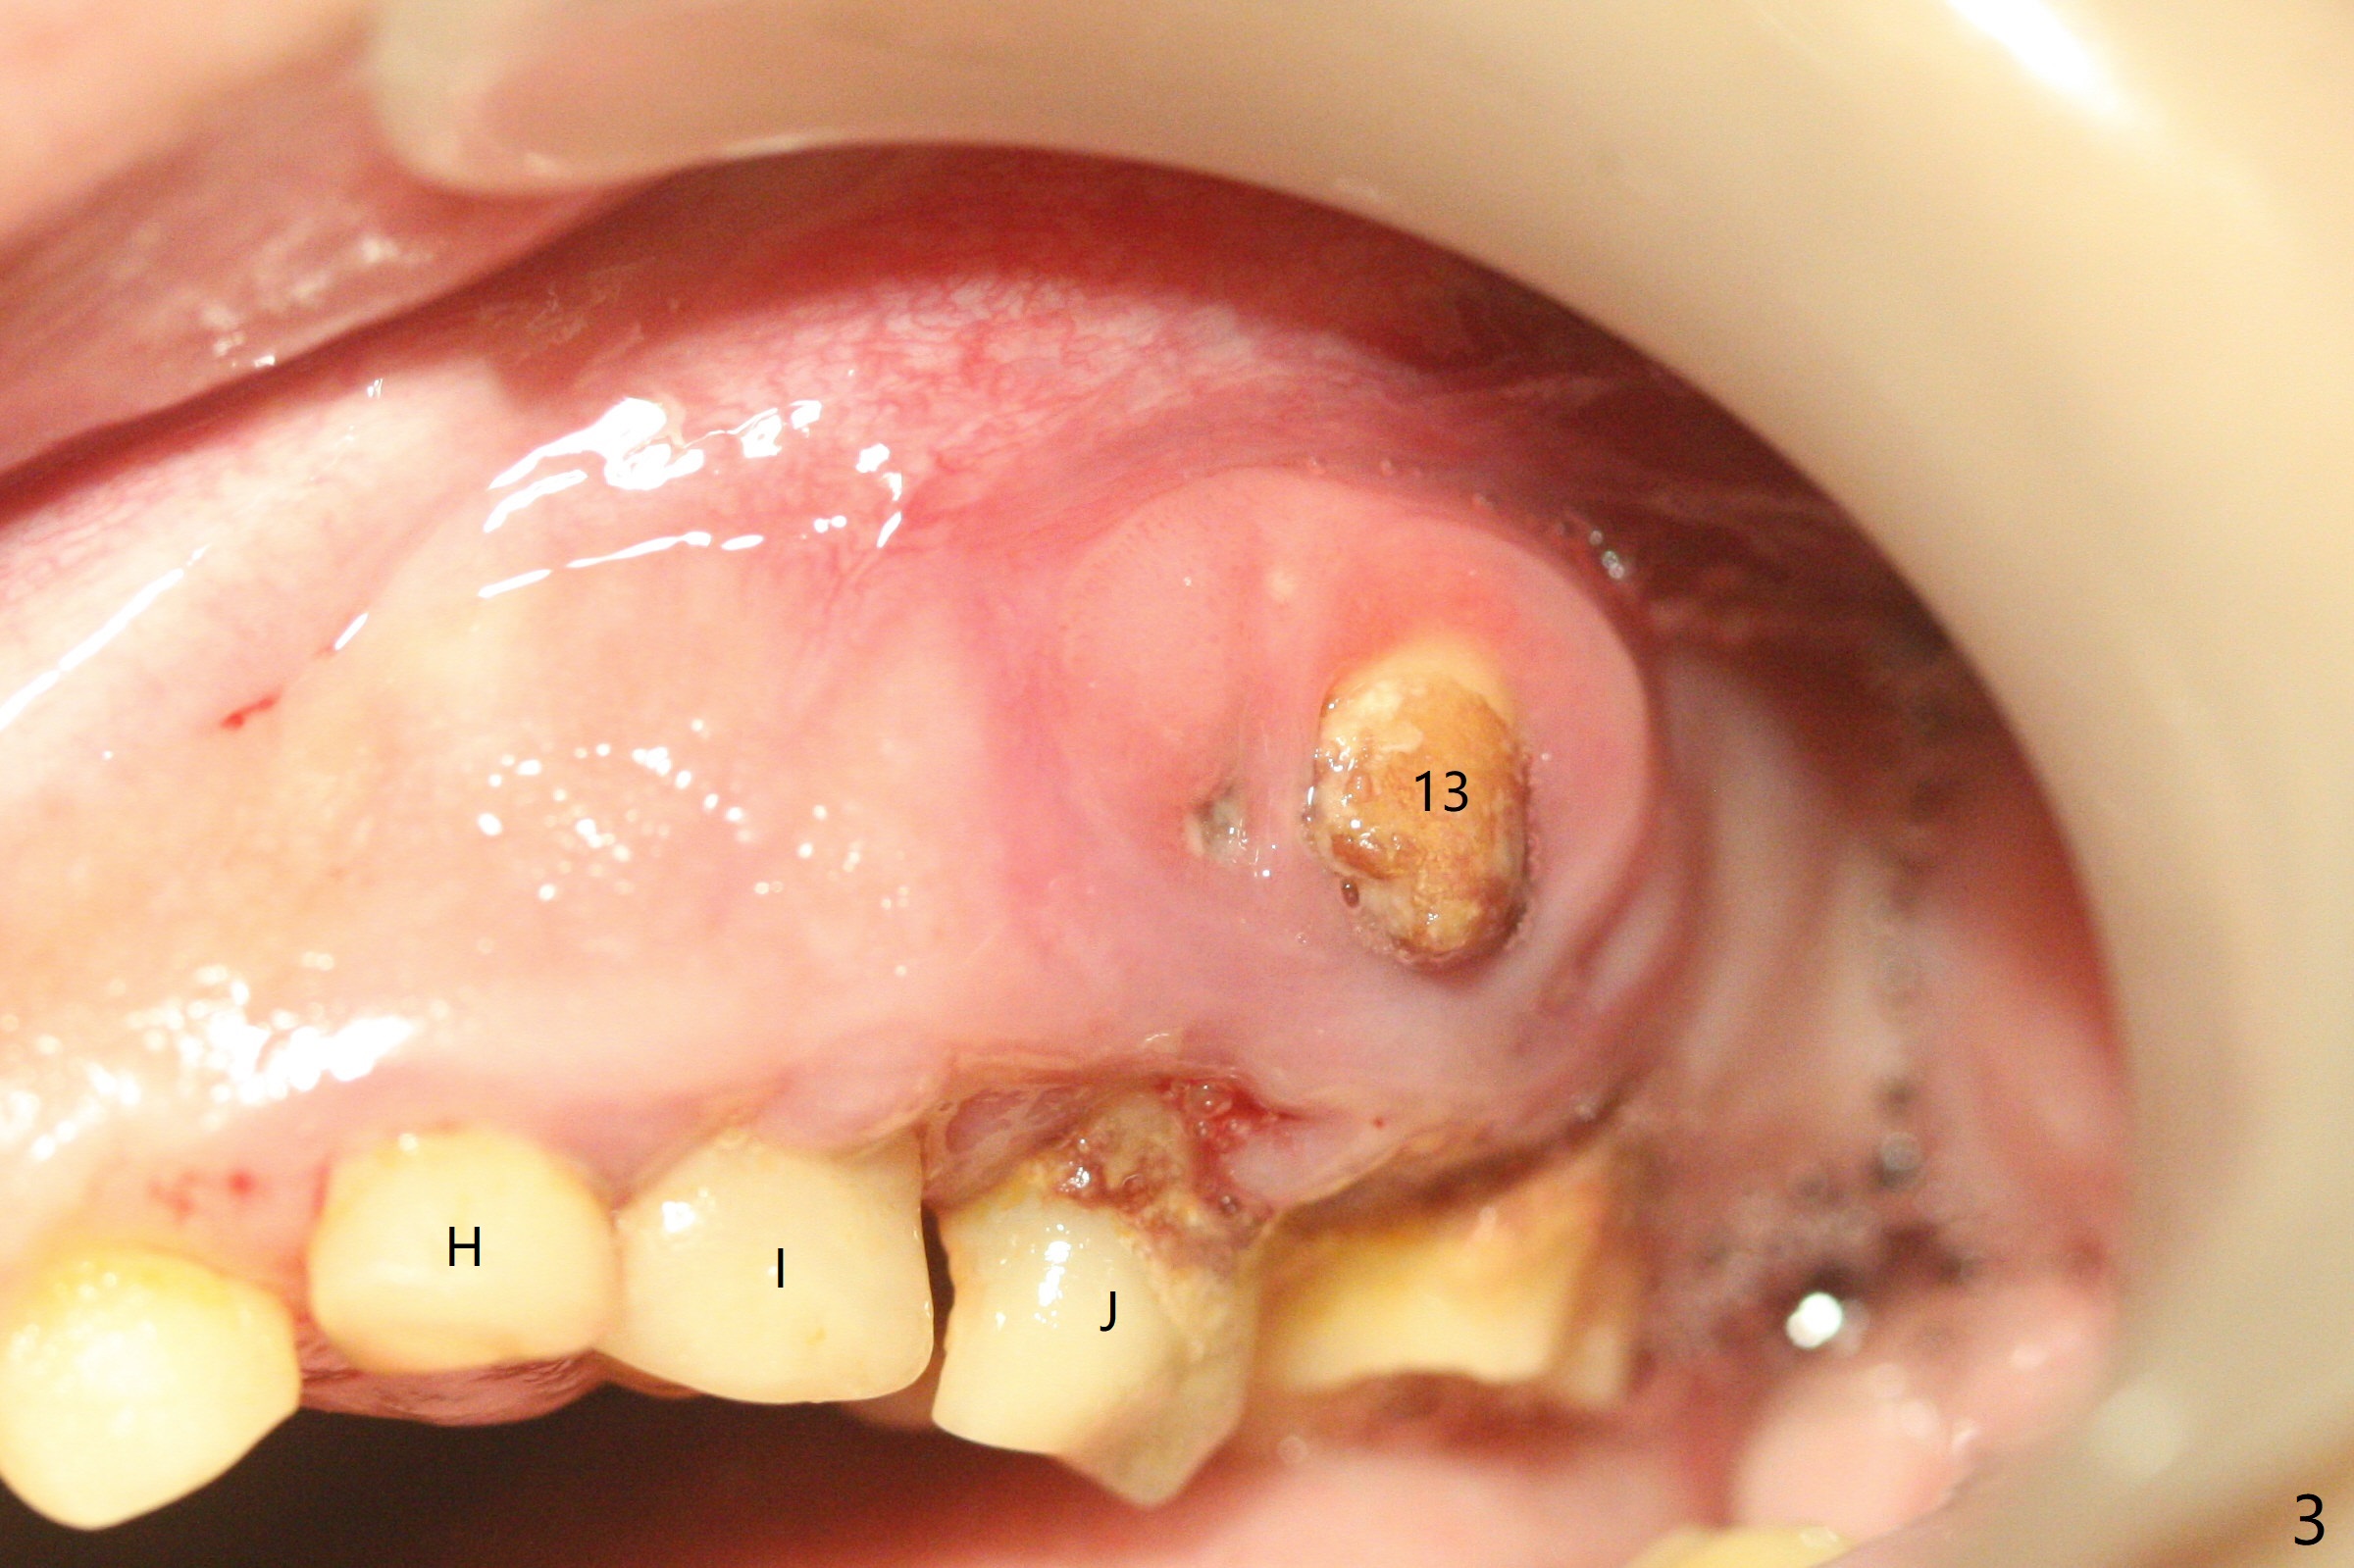

13岁男孩,每颗乳恒牙交换时乳牙都需要拔除,萌出的恒牙个子小,侧切牙反合(图二,五),对冷热敏感,不爱刷牙,口腔卫生欠佳(图三:13(结石)),父母要求诊治。今天在局麻下,左上洁治,没有局麻区域无法洁治,敏感,并且拔除H-J。S下沉,5,28埋伏(图七),其余乳磨牙都有龋齿。如何治疗?是釉质发育不全?暴露5,28前将拍摄CT。